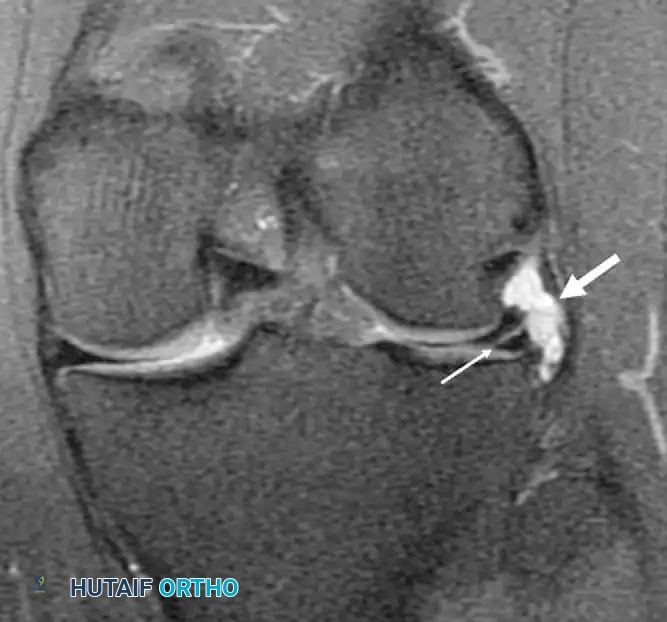

While plain radiographs (weight-bearing AP, lateral, Rosenberg, and skyline views) are essential to rule out osteoarthritis or loose bodies, Magnetic Resonance Imaging (MRI) is the gold standard for diagnosing meniscal tears. MRI accurately delineates tear morphology (horizontal, longitudinal, radial, root, or bucket-handle) and assesses the integrity of the cruciate ligaments.

Meniscal root tears (avulsions of the meniscal attachment to the tibial plateau) completely disrupt hoop tension, leading to rapid meniscal extrusion and catastrophic joint overloading.

Postoperative healing of the root to the bony footprint restores hoop tension and prevents meniscal extrusion, halting the rapid progression to osteoarthritis.